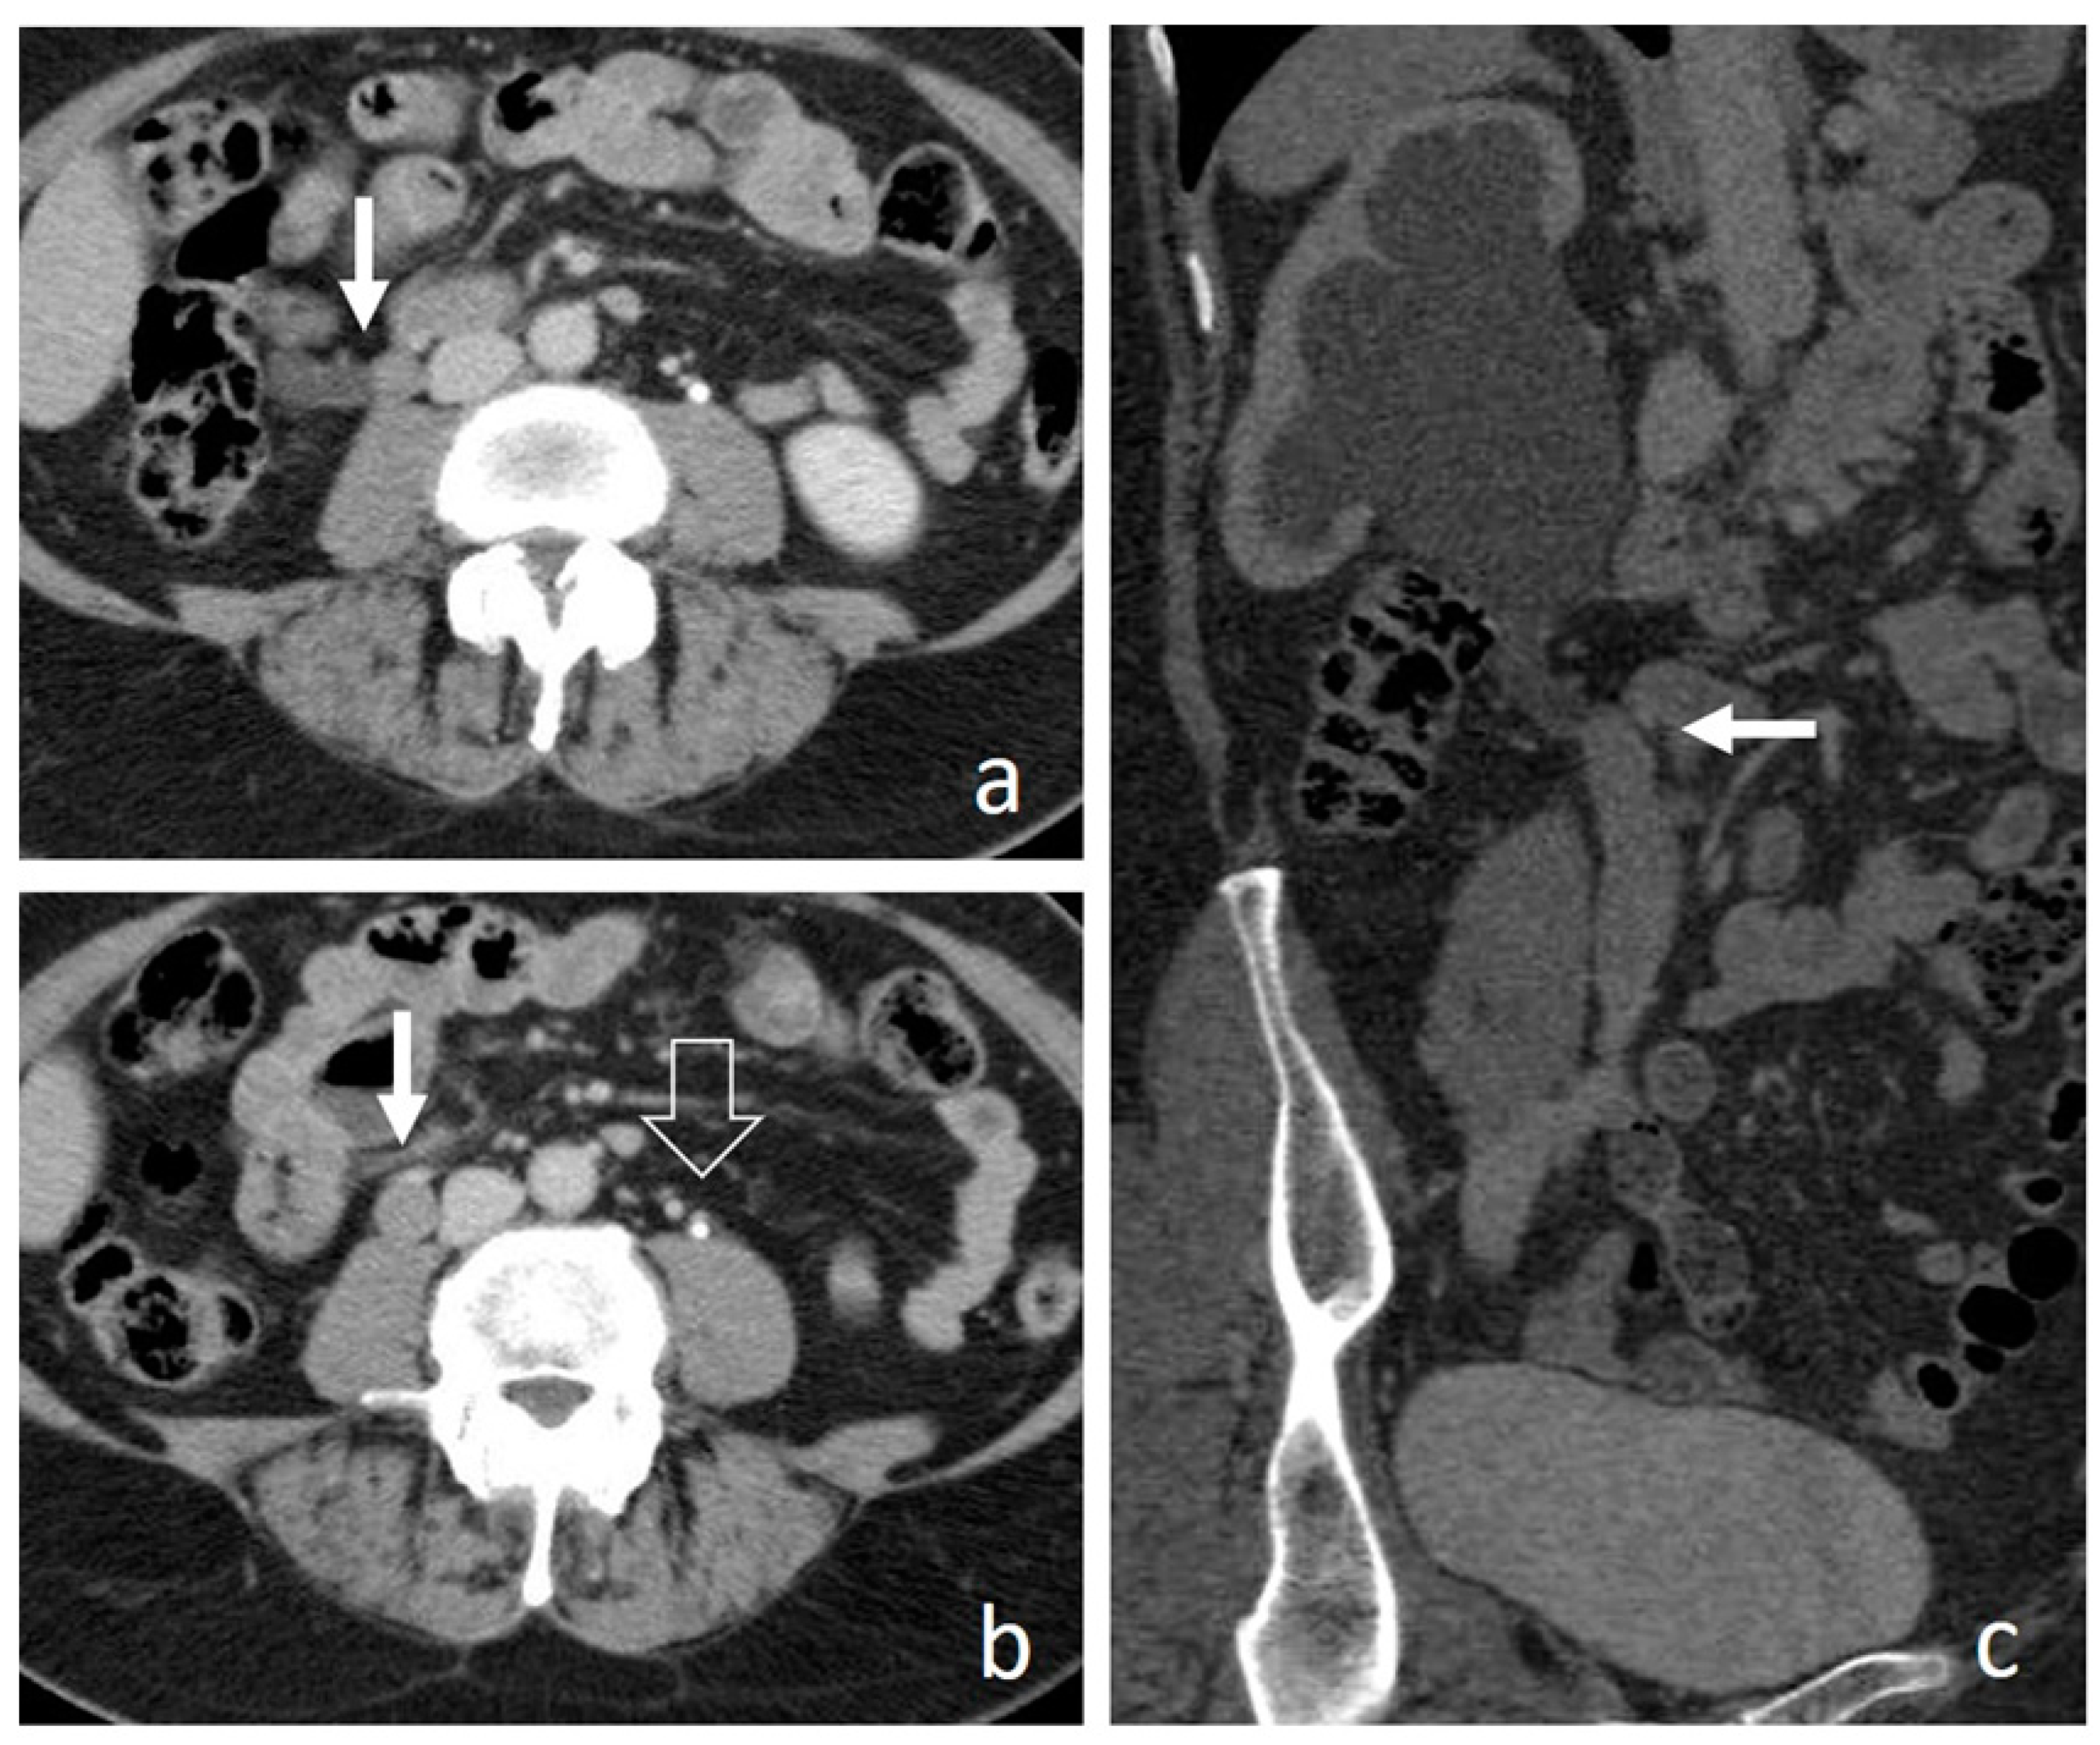

4.7. Pyeloureteritis Cystica